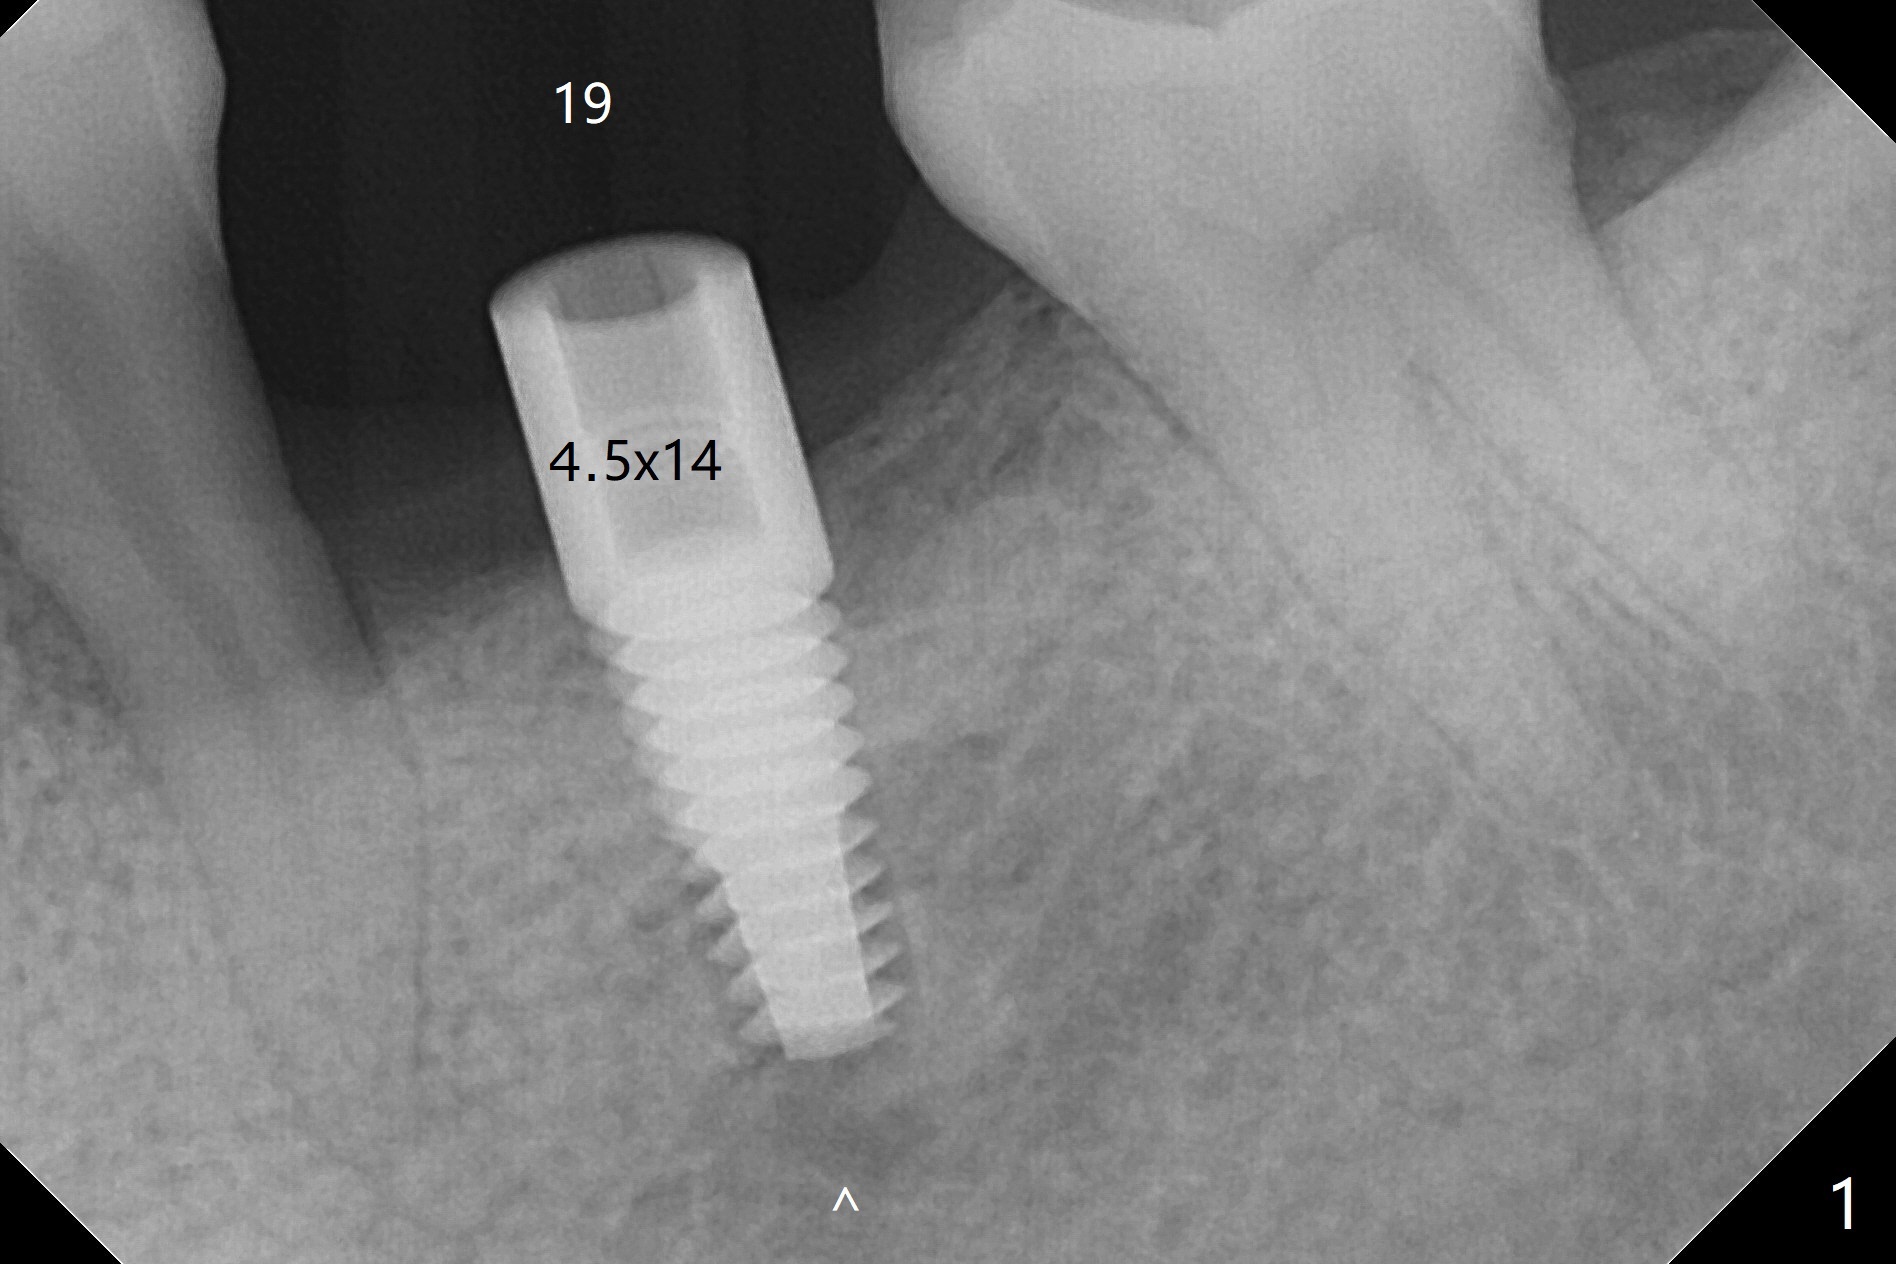

After 4x11.5 mm drill with 10.5 mm offset for bone-level implant at #19, a 4.5x14 mm tissue-level tapered tap is used with high torque. The same sized implant is placed in-completely with apical space (Fig.1 ^). Following reuse of the guide and 4.5x7.3 mm drill, the implant is placed deeper easily (Fig.2-4). The implant threads are subcrestal buccally (B (L: lingual plate), as compared to design in Fig.3'). Later the implant is placed a little deeper with insertion torque of 25 Ncm. There is no crestal bone loss 4 months postop (Fig.5). Waterlase is used for gingivectomy without anesthesia or burn after placing a 4x5 mm abutment. The access is difficult due to severe bone loss. There is no gap between the implant threads (osteointegration) 9 months postop/immediate post cementation (Fig.6 < (coronavirus)), although the crestal bone has lost. After cementation, the tooth #20 has no mobility; note bone loss around the root of #20 (Fig.5). In spite of the residual cement, there appears no bone loss 2 months postop (Fig.7). Instead the distal crestal bone is more organized.